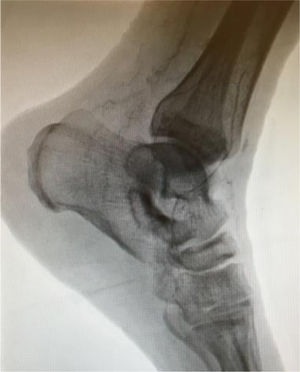

En seguida, todos los pacientes son sometidos a eco-Doppler arterial y venoso. Este examen es clave en la evaluación inicial del paciente, proporcionando información sobre el tipo de enfermedad, el influjo del bypass y las arterias diana. El mapeo venoso nos permite identificar venas autógenas de diámetro adecuado. Un diámetro mínimo de 3mm es ideal para la mayoría de las revascularizaciones, pero aceptamos venas entre 2,5 y 3mm para bypass a arterias inframaleolares. Preferimos un segmento único de safena interna, pero consideramos venas alternativas y, en último caso, anastomosar 2 segmentos venosos de buen diámetro.

La fase siguiente de la planificación es la angiografía convencional diagnóstica, que realizamos sistemáticamente, excepto en pacientes con enfermedad renal crónica avanzada (depuración de creatinina <30ml/min). La inyección de contraste (80cc, 6ml/s, 600PSI de presión), se realiza mediante una punción femoral retrógrada con introductor 4F. Esta técnica permite el reclutamiento de todos los colaterales responsables de la irrigación de la pierna y del pie, desde la arteria femoral profunda, obteniendo así un gran detalle anatómico (fig. 2).

La calidad de la angiografía es crucial para la planificación de cualquier revascularización distal o ultradistal, con imágenes en 2 proyecciones y tiempos de exposición prolongados que permitan visualizar las arterias del pie. Los tiempos de exposición pueden alcanzar los 60s y, como tal, nos parece esencial la realización/supervisión de este examen por parte de un miembro del equipo con experiencia en este tipo de revascularización, con el fin de optimizar el uso de la radiación y disminuir la cantidad de contraste. En pacientes con contraindicación para la angiografía, se realiza la planificación basada exclusivamente en los hallazgos del eco-Doppler.